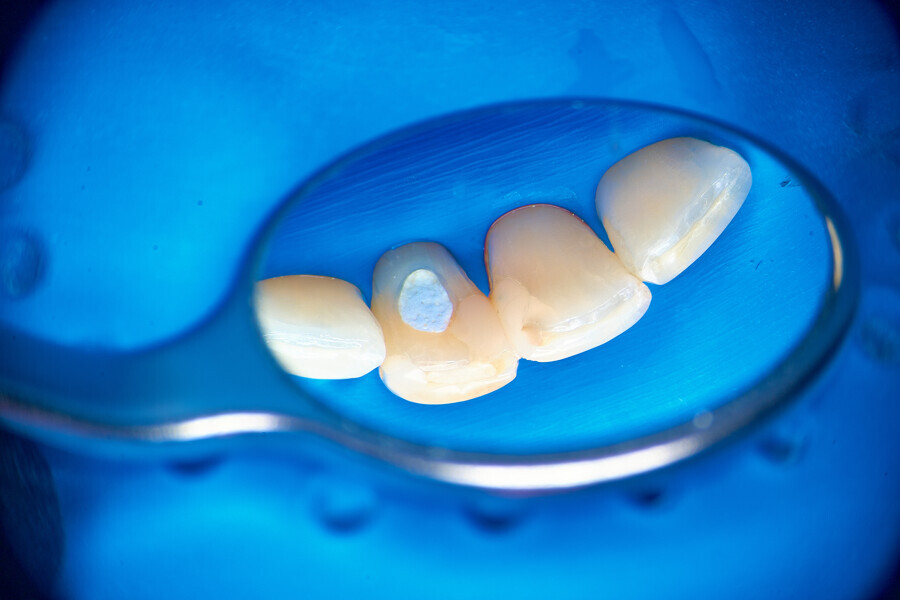

A deep split in the canal is always challenging, especially in situations where there is compromised access or limited space. The patient came to Dr Witkowski’s dental office for a routine procedure of caries removal and restoration (Fig. 14). An initial radiograph was performed (Fig. 15). Initial removal of caries was performed, and a gingivectomy was also done owing to a deep carious lesion in the subgingival area mesially (Fig. 16). After isolation, restoration of the mesial wall was performed according to the standard protocol. After this, the access cavity was reshaped with ultrasonic tips (Fig. 17).

Instrumentation was then performed with the R25 RECIPROC blue up to the level of the split, and the split was prepared with the 12.5/0.04 R-PILOT (VDW; Fig. 18). The final irrigation protocol was performed with copious amount of fluids (sodium hypochlorite and citric acid with a final rinse of distilled water; Fig. 19). Obturation was performed with the piston technique, and the restoration was done with composite material (Fig. 20). The patient was referred to the prosthodontist for final restoration. On the final CBCT scan, it was clearly visible that the piston technique had helped to obturate the deep split in the apical area (Fig. 21).